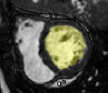

4.3.2 Analysing Heart Function in 4D MRI

Four-dimensional imaging of patient anatomy is gaining interest in the medical community. The temporal analysis of anatomical structures is used to extract the characteristics of related dynamic processes, which often indicate certain pathologies [16, 26, 3]. In this section, we apply nWESD to the shapes of the hearts extracted from four dimensional cardiac images of five different patients. The scan of each patient captures a full cycle of one heartbeat as a series of 20 3D images. Each image shows the left ventricle (LV) at a specific point in the cycle, from which we manually segment the corresponding blood pool. Our reference is the blood pool extracted from the first frame (diastole). We compute the nWESD scores between this reference and all other shapes extracted from the series of images. Here, we do not normalise the eigenvalues with respect to the global scale since size change is an important aspect of the heartbeat dynamics. The graph given in Figure 8 shows the results of these measurements over time across the five patients. The figure also shows some exemplary images and shapes. We observe that the symmetry of the heartbeat along the systolic (as the blood pumps out of the LV pool) and the diastolic phases (as the blood fills in the pool) is well captured with the nWESD score. Furthermore, the end-systolic phase (the time point with the largest distance w.r.t. the reference) is at different time points for different patients, which is to be expected since the different patient scans are not synchronized in time. In summary, WESD well captures the dynamics of the beating heart, which is to be expected given the continuous link between the differences in eigenvalues and the difference in shape (see Section 2).